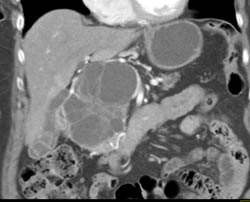

Cystadenoma